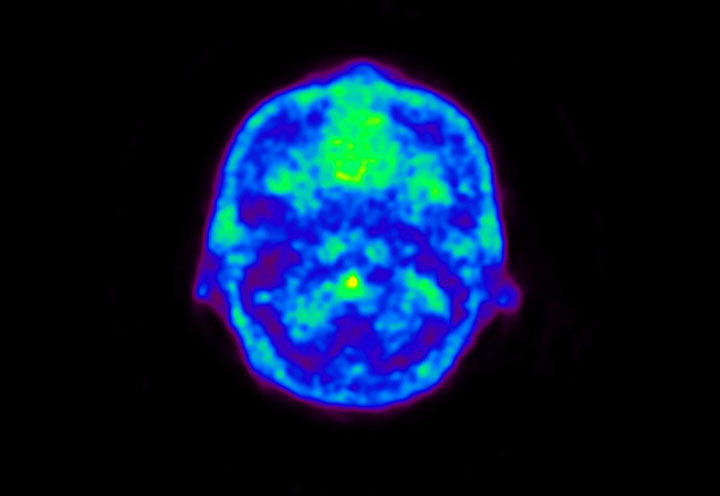

Head / Case5 : Amyloid

Courtesy : Kindai University Hospital

- Imaging protocol

- Injected dose: 4.27 MBq/kg, 18F-Flutemetamol

- Uptake time: 99 minutes

- Scan time: 20 minutes